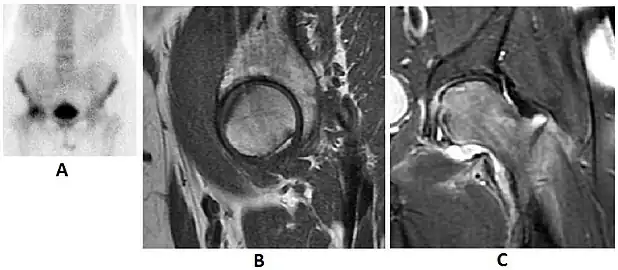

Radiological signs of transient osteoporosis of the hip include localized osteoporosis of the femoral head and neck (Figure 8). Nevertheless, final diagnosis has to be made with MRI to differentiate it from avascular necrosis and from insufficiency or stress fractures of the femoral head or neck. In case of AVN, radiographs can only demonstrate delayed or advanced signs. Staging according to Ficat classification ranges between normal appearance (stage I), slight increased density in the femoral head (stage II), subchondral collapse of the femoral head with or without “crescent” sign (stage III), and advanced collapse with secondary osteoarthritis (stage IV). In the case of stress or insufficiency fractures X-ray sensitivity has been proven to be much lower than MRI, which is currently the gold standard.[1]

Figure 8:

-

X-ray of a patient with transient osteoporosis of the left hip showing osteoporosis.[1] -

Coronal stir imaging in transient osteoporosis, showing diffuse edema.[1] -

Scintigraphy (A), sagittal T1 (B), and coronal PD fat sat of a patient with a subchondral fracture of the femoral head with convex shape to the articular surface.[1] -

Coronal T1 of a patient with avascular necrosis of the femoral head.[1]